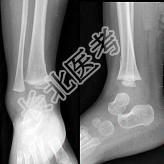

- 单项选择题患者男性,10岁, 外伤后感患处疼痛,根据所提供图像, 选择最佳选项 ( )

A、骺移骨折

B、踝关节脱位

C、腕关节脱位

D、未见异常

E、青枝骨折